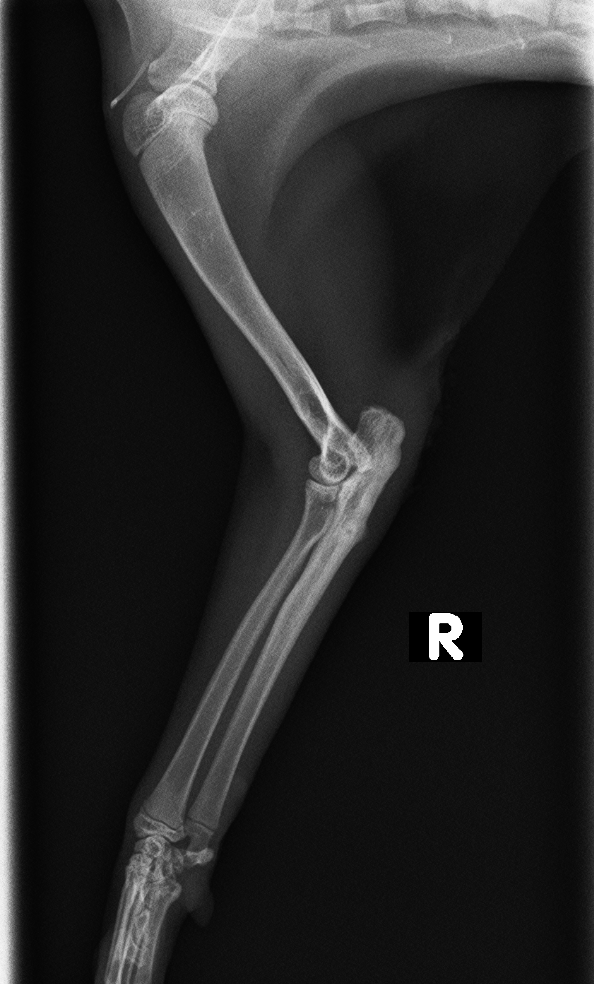

レントゲン検査より、右肘頭骨折が認められた

before